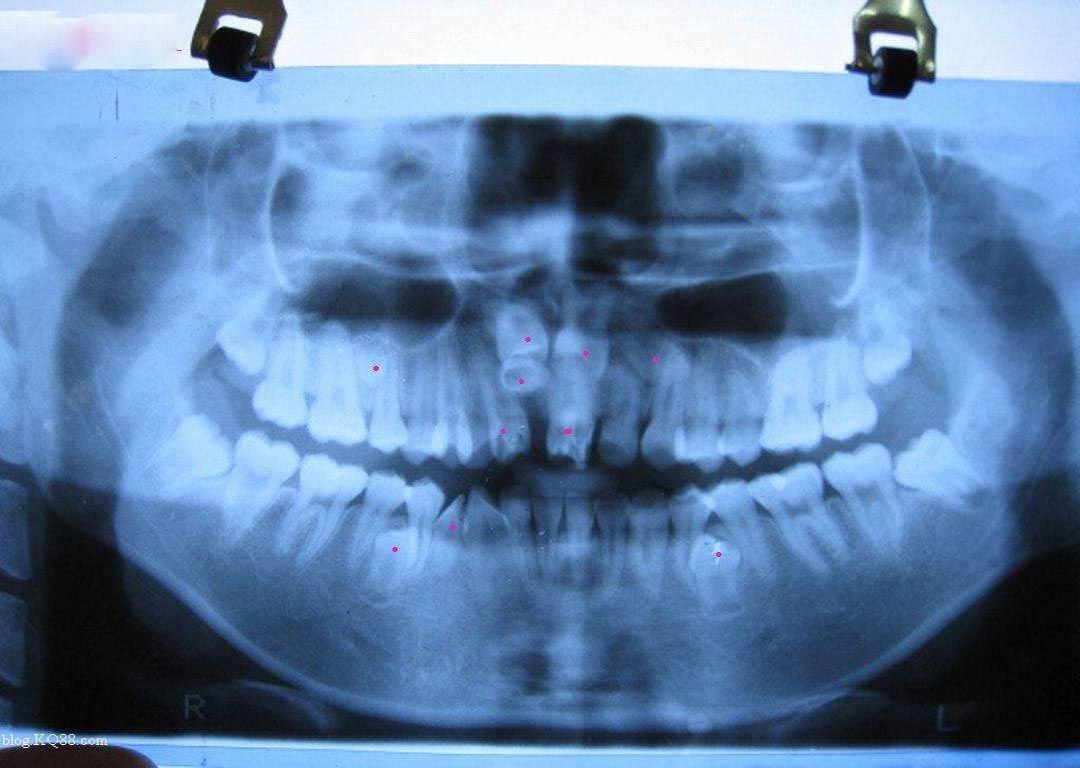

当然多生齿还分为两种,第一种就是萌出口腔的多生齿,这种的话肉眼是可以看到的;还有一种就是埋伏性多生齿,就是埋伏在颌骨中没有冒出头的多生齿。这种多生齿需要在X光的检查下才能看出来,所以这种多生齿处理起来也是相当麻烦,处理的费用也是第一种的五倍左右。那么家长就有可能有这样一种疑问了,宝宝毕竟是要换牙的,可不可以不用处理呢?

但各位家长们看到这里也不必惊慌,多生齿是孩子中非常常见的牙齿变异,很多宝宝在小的时候都会得这样的病。虽然它本身其实并不那么可的,但“未知”和“已知”还是有可能会给孩子带来一些隐患。首先“未知”是指在这种情况下,不能知道孩子到底已经长了多少多生齿,因为这种牙齿生长的时候宝宝是不会感觉到疼痛的,所以只有在拍X光时才有可能会被发现;而“已知”则是有时候虽然家长知道自己孩子已经长多生齿了但并没有放在心上,以为只是多长了两颗牙齿罢了,以后乳牙脱落的话它也会掉的。但其实这种观念是非常不正确的,如果任由它发展下去的话迟早有一天会影响到恒牙的生长状况,最终导致牙齿不正常。